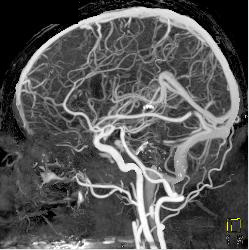

CTA With Dual Energy and Bone Removal